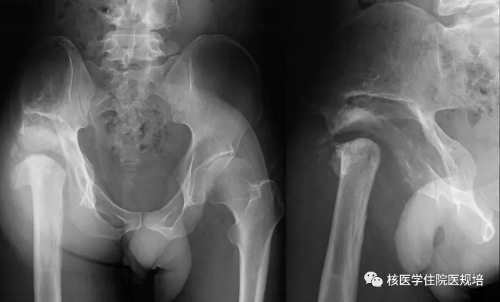

患者男性,30岁, 3个月前无明显诱因突发大小便失禁,同时伴下肢活动障碍,为进一步诊治就诊于我院。既往史:出生后诊断为先天性无痛无汗症,其他无特殊病史。查体:患者轮椅进入病房,神志清楚,对答切题;全身皮肤干燥、见多处瘢痕,皮肤痛觉缺失,指甲发育不良,脊柱生理屈度存在,无明显棘突压痛。双上肢未见明显畸形,肌力、肌张力未见明显异常。左下肢可见膝关节不规则隆起,表面不光滑,质硬,无波动感,关节屈伸正常,局部皮温正常,无皮肤红肿、破溃或静脉怒张,压痛(-);右下肢未见明显异常。双下肢感觉较弱,巴氏征(-)。实验室检查无明显异常发现。腰椎X光片及CT(图1.2)检查发现腰椎退行性变,L3、L4椎体融合,骨小梁结构模糊,L5/S1椎间盘膨出,前纵韧带钙化;多关节部位X光片示右髋关节(图3)髋臼扩大、骨质吸收,股骨头脱位,骨骺未融合,残端如刀削状,关节肿胀,内见多发碎骨片;左膝关节(图4)正常关节结构消失,关节对位差,骨端膨大,周围见多发游离骨块,股骨下段、胫骨平台见骨质破坏,关节周围软组织肿胀;右踝关节(图5)诸骨在位,胫腓骨远端膨大变形,距骨变扁,诸骨骨质密度弥漫减低,骨小梁稀疏,内外踝边缘可见骨质增生;关节间隙狭窄。为进一步了解全身骨病变情况行99mTc-MDP全身骨显像(图6)。

图3.

图4.